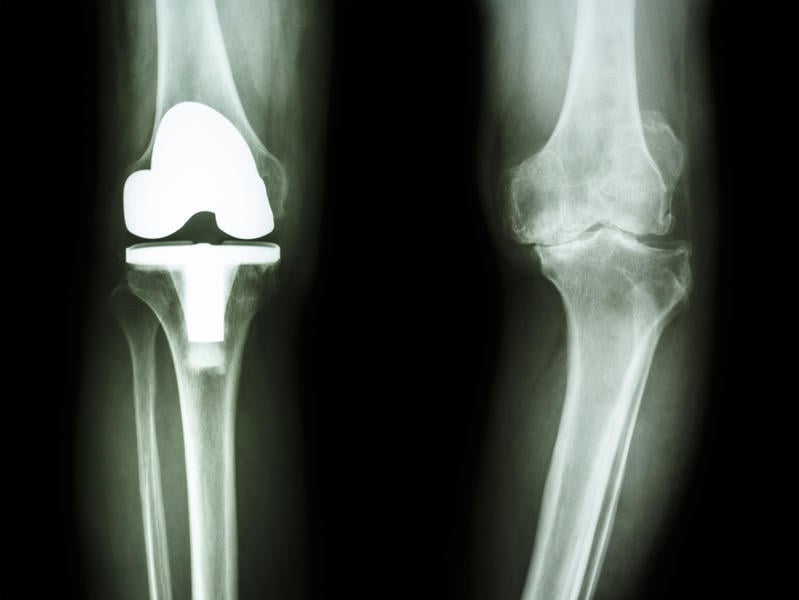

film radiographie du genou de l'arthrose patient du genou et articulation artificielle

Si elle est parfaitement maîtrisée par les chirurgiens, la pose d'une prothèse de genou présente souvent des suites postopératoires plus ou moins longues au cours desquelles le risque que des complications surviennent n'est pas nul.